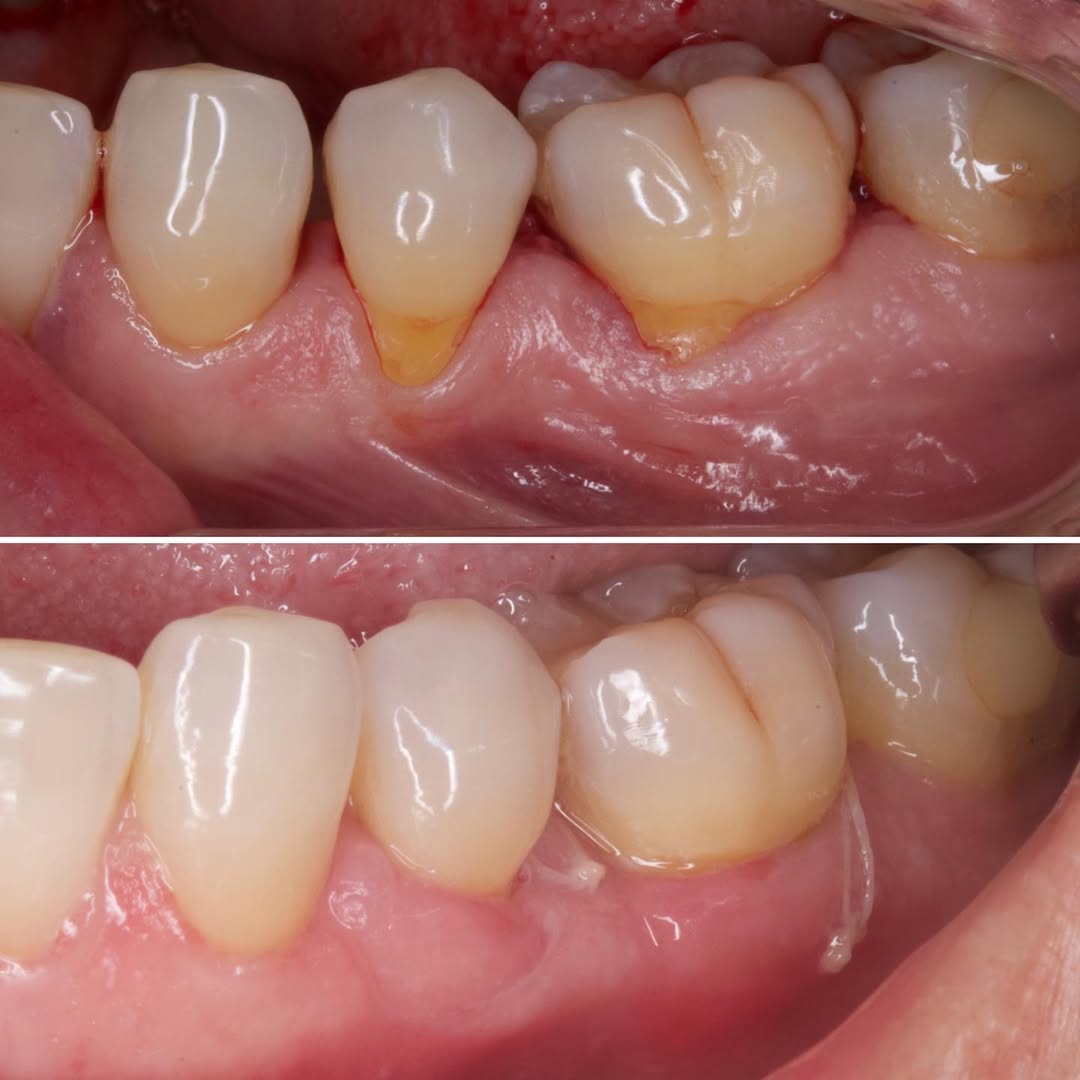

Podrás asistir a la planificación de casos y cirugía de injerto de tejido conectivo. Factores determinantes y elección de la técnica adecuada. Sumérgete en un protocolo predecible y técnicamente correcto para obtener resultados óptimos.

Una estancia clínica pensada para quienes quieran iniciarse o dar un paso más en el campo de la cirugía mucogingival. Durante esta experiencia tendrás la oportunidad de aprender en directo cómo se planifica y se lleva a cabo una cirugía mucogingival mediante técnica de Túnel.

La sesión

Formación teórico-práctica completa sobre las técnicas más avanzadas en cirugía mucogingival. Durante dos días intensivos, los participantes aprenderán desde la evidencia científica y la anatomía de las zonas donantes hasta la ejecución de injertos, cubrimiento radicular y aumento de